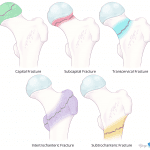

- Subcapital femoral neck fracture